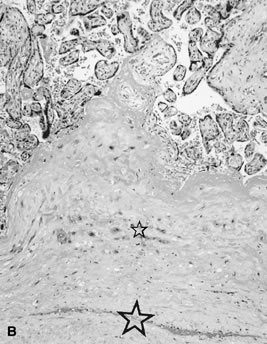

Placenta creta is a clinical diagnosis based on difficulty of delivery of the placenta. If the placenta is delivered and examined pathologically, areas of “incompleteness” of the maternal surface can be noted. The range of findings can extend from missing segments of the placenta to focal irregularities of the basal surface. At the edges of incomplete areas, histologic examination may yield smooth muscle (Fig. 10).61,62 This may be the only confirmation of a diagnosis of placenta creta that can be made when only the placenta is submitted to pathology. If a postpartum curettage or hysterectomy specimen is available, the diagnosis is usually confirmed. Histologically, the lesion may be very focal, with absence of decidualized endometrium, and villi implanted directly onto the myometrial smooth muscle (Fig. 11). The invasive trophoblast can be distinguished from endometrial stromal cells by immunohistochemistry; trophoblasts are cytokeratin positive and endometrial cells are vimentin positive. In a set of 462 births at less than 32 weeks' gestation and 108 singleton uncomplicated births at more than 37 weeks' gestation, excluding stillbirth, multiple gestation, chronic hypertension, diabetes mellitus, and fetal congenital anomalies, 44 of 462 (9.5%) of the preterm placentas had basal myometrial fibers versus 0.9% (1/108) of term controls (p < .001). Uteroplacental vessels with abnormal physiologic change were more frequent in cases with myometrial fibers (p < .003), and placental weights were lighter (p < .03). The incidence of basal myofibers was similar in preterm preeclampsia, premature membrane rupture, preterm labor, and nonhypertensive abruption.61 Experimental models suggest that cytotrophoblasts proliferate in response to hypoxia63,64 and may also directly migrate in response to local oxygen tension.65 One response to local hypoxia may be deeper myometrial invasion. Most of the foci of basal myofibers in our data set were found in the immediate vicinity of a uteroplacental vessel with incomplete or absent physiologic conversion. Basal myofibers may indicate local placental hypoperfusion that has prompted local deeper cytotrophoblast invasion.

Fig 10. Term placenta with adherent smooth muscle ( large star ); note abundant invasive trophoblast ( small star) (hematoxylin and eosin, ×10).

Fig 11. A. Postpartum hysterectomy specimen. Normal implantation site with invasive trophoblast ( small star ), maternal decidua ( intermediate star ), and myometrium ( large star) (hematoxylin and eosin, ×10). B. Postpartum hysterectomy specimen. Placenta accreta with implantation of villi onto myometrium ( large star ). Few invasive trophoblasts ( small star) and no maternal decidua (hematoxylin and eosin, ×10).